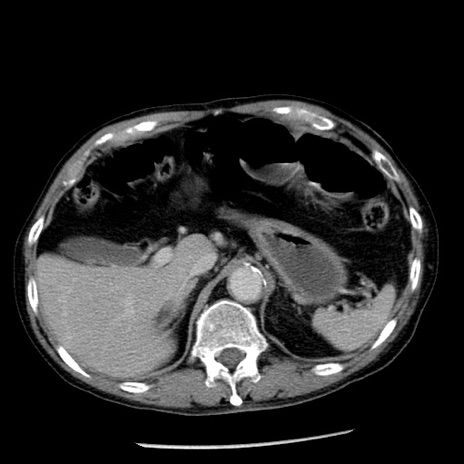

症例26(横断像)

【症例】80歳代男性

【主訴】嘔吐

【現病歴】昨晩2回嘔吐あり、今朝になっても嘔吐あり。来院。

【既往歴】胃潰瘍

【身体所見】意識清明、BT 37.6℃、BP 166/95mmHg、HR 100bpm、SpO2 97%、腹部:平坦・軟、腸蠕動音聴取良好、圧痛なし。

【データ】WBC 21900、CRP 1.46